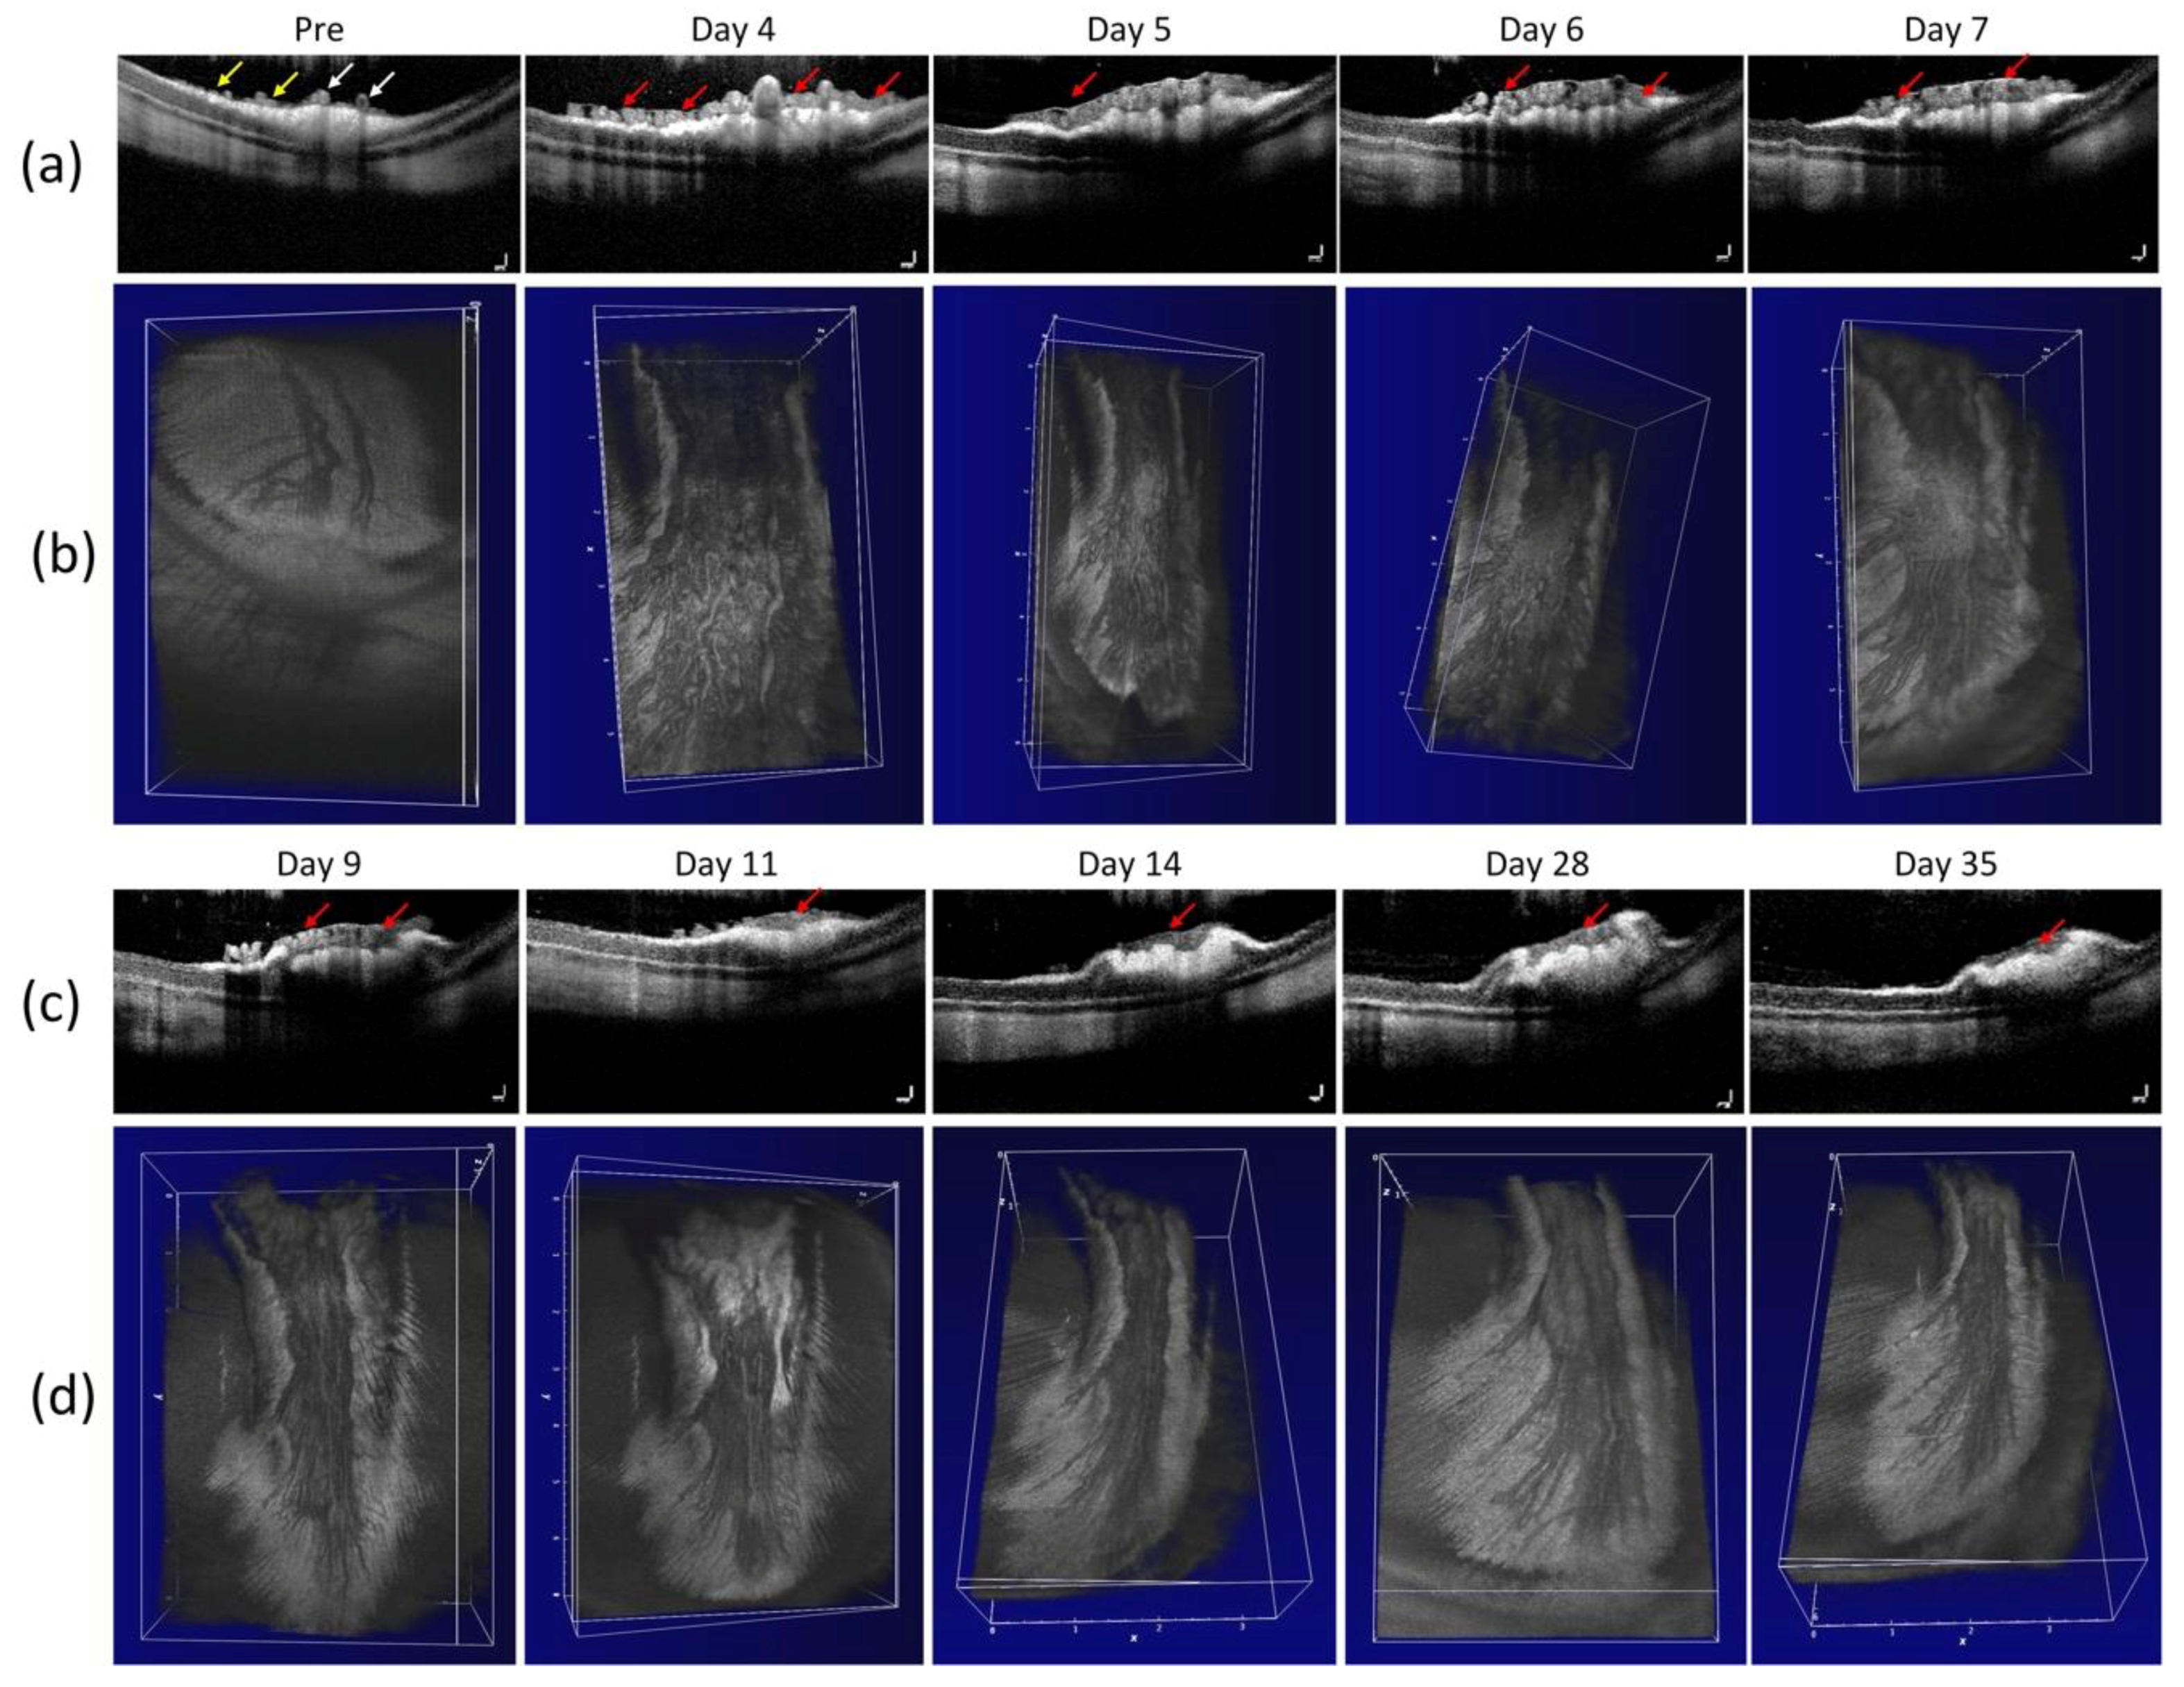

Figure 3. In vivo evaluation of a retinal neovascularization. (a,c) Cross-sectional B-scan OCT images acquired along the scanning lines from Figure A1. The OCT image showing choroidal vessels (CVs), retinal vessels (RVs), retinal neovascularizarion (RNV) and retinal layers. Yellow arrows show the position of the existing retinal blood vessels. Red arrows depict the location of RNV. (c,d) 3D volumetric OCT images for the retinal neovascularization.

Figure 3 exhibits the cross-sectional B-scan OCT images acquired along the dotted lines shown on the color fundus image in Figure A1. These OCT images were performed at different times before and after the RNV model and reveal the formation of new blood vessels. These OCT images present the change in the retinal layers. The yellow arrows show the position of the major retinal vessels whereas the red arrows indicate the position of RNV. Similar to color fundus and FA images shown in Figure 2, these OCT images demonstrate that the RNV was significantly increased at days 4, 5, 6, and 7. Then the RNV gradually decreased from day 9 to day 35. In addition, nerve fiber layers were obviously enlarged in comparison to control images. In addition, no retinal detachment was observed on the OCT image. This demonstrates that OCT can potentially visualize the formation of RNV. Figure 3c,d represents 3D OCT volumetric images of the retinal neovascularization. The OCT volumetric images clearly display a branching network of retinal neovascularization.